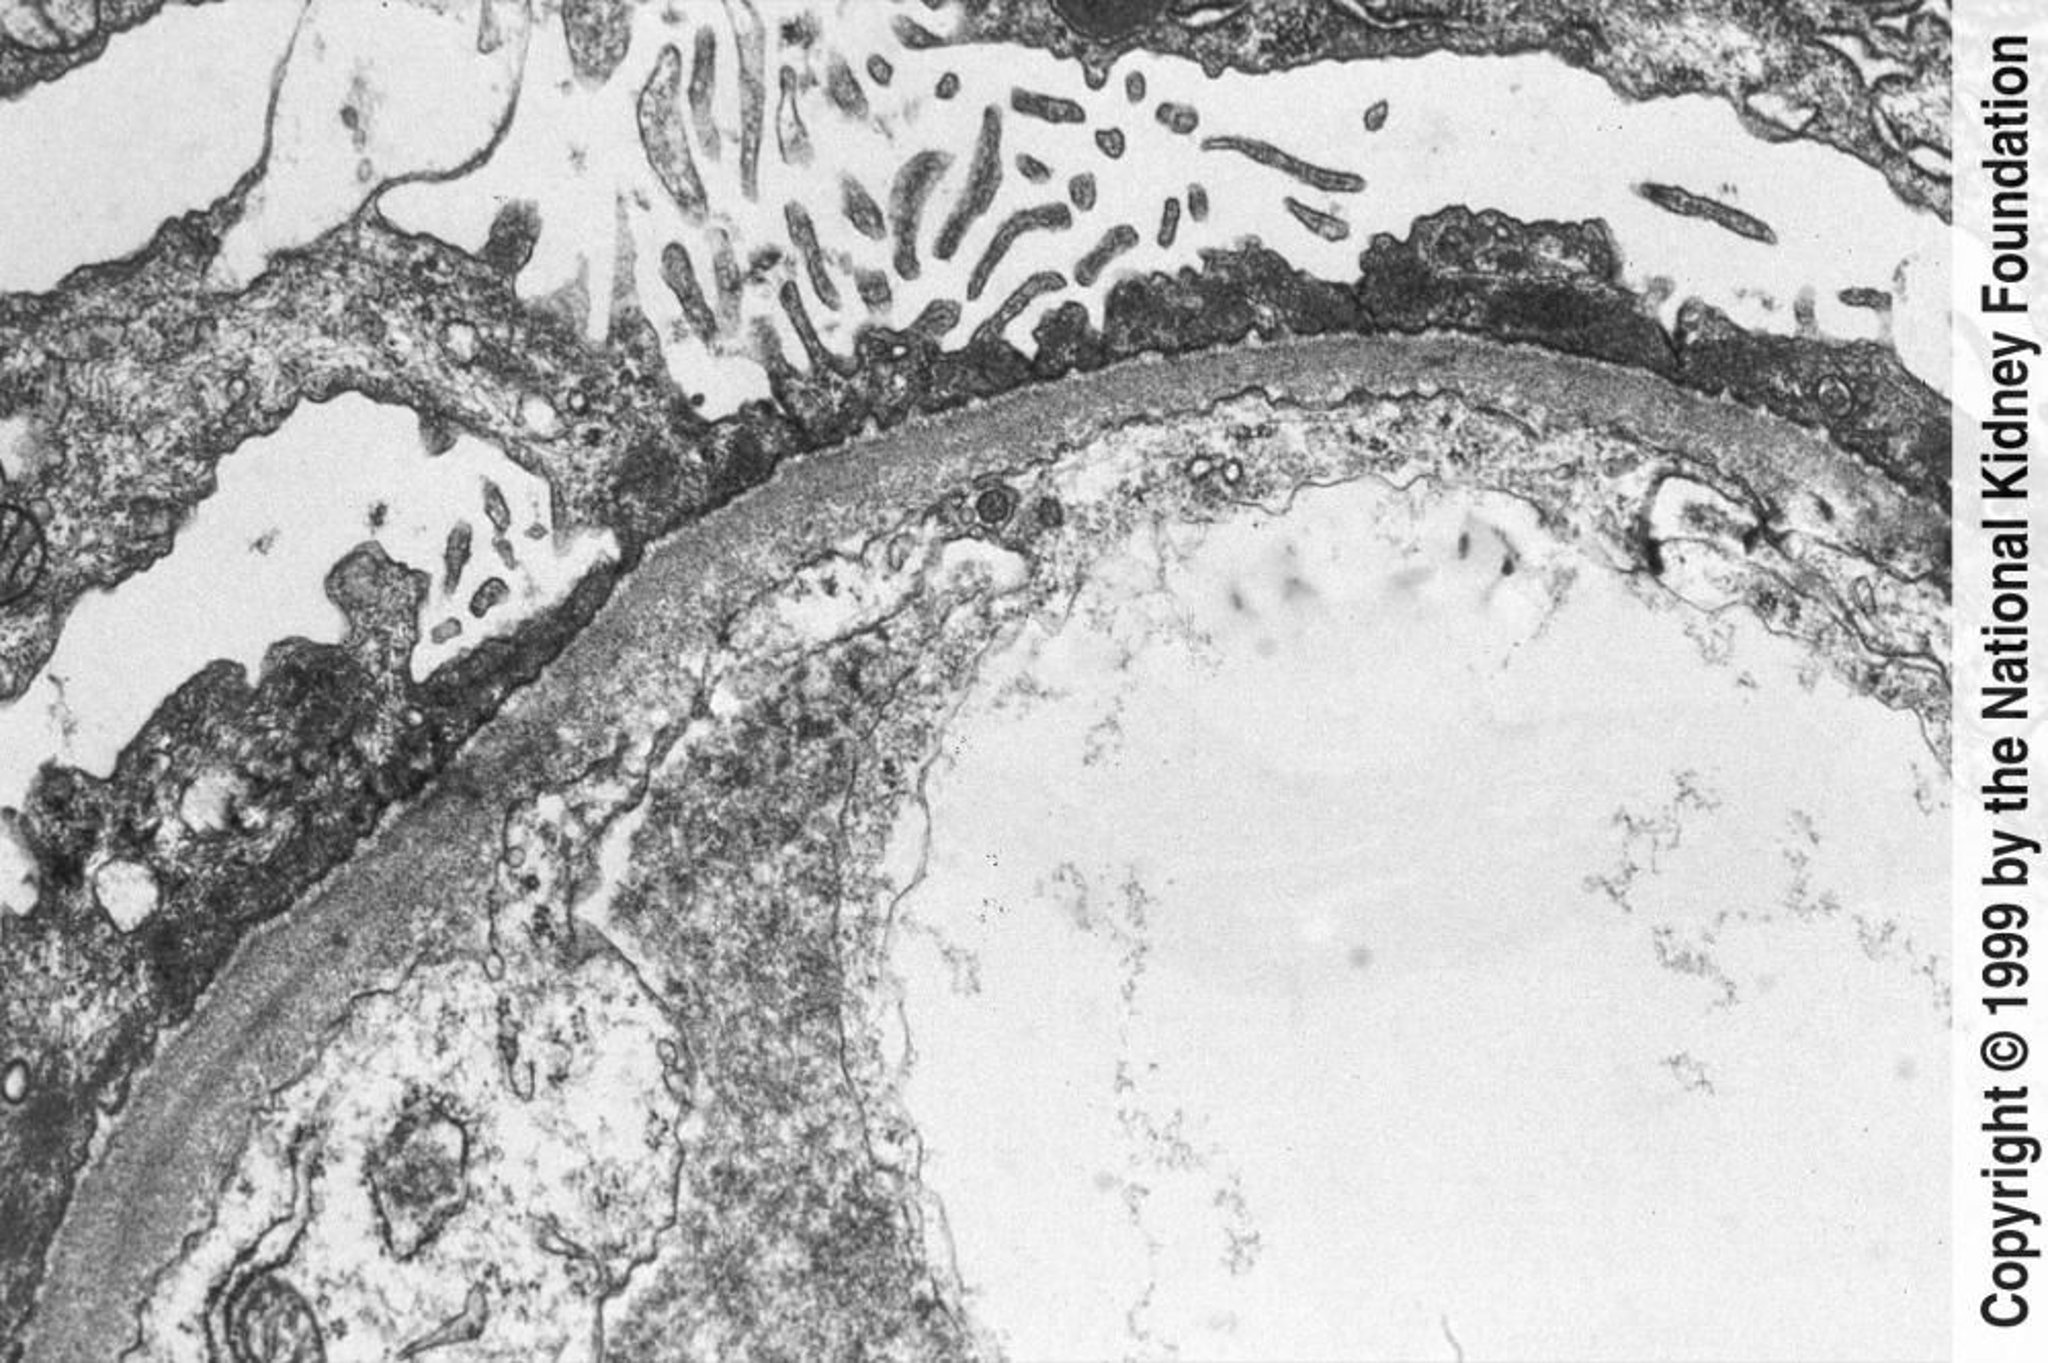

La biopsia renale è indicata in adulti e bambini con manifestazioni atipiche. La microscopia elettronica mostra edema con diffuso rigonfiamento (o scomparsa) dei processi podocitari (vedi figura Caratteristiche in microscopia elettronica delle patologie immunologiche glomerulari). Complemento e depositi di Ig sono assenti all'immunofluorescenza. Sebbene la scomparsa dei podociti non si osservi in assenza di proteinuria, si può avere un'elevata proteinuria con processi podocitari normali.

Caratteristiche in microscopia elettronica delle patologie immunologiche glomerulari